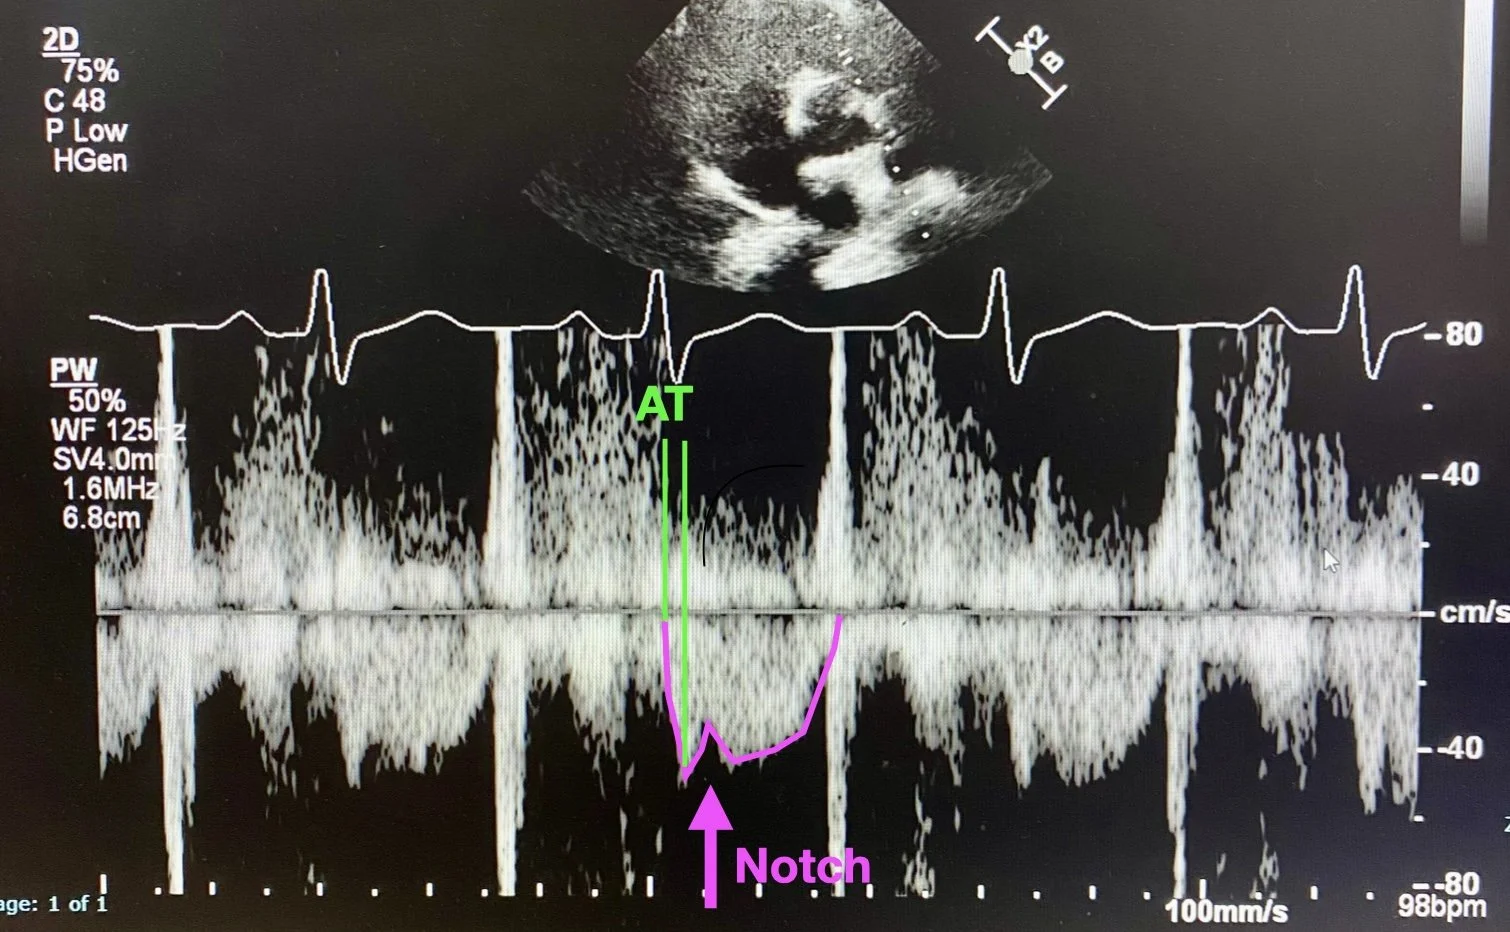

The use of doppler signal can detect RV outflow in the RVOT and pulmonary trunk. Obtain a parasternal short axis, at the level of the aortic valve. The RV wraps around the top of the valve with the pulmonary valve typically sitting at 2-3 o’clock to the aortic valve (see diagram below). By placing PW doppler in the RVOT (just before the pulmonary valve) you will get the RVOT tracing.

A normal RVOT trace is triangular, and the Acceleration Time (time from start to peak) should be >100ms (assuming a relatively normal HR). In acute PE you see features of raised pulmonary pressures which include:

• Notching of the RVOT doppler trace

• Short acceleration time (often around 60ms in acute PE)

In the left hand diagram (PSAX view) you can see the right heart ‘wrapping around’ the aortic valve in the centre. Place PW Doppler just before the pulmonary valve.

The right hand diagram shows the PW doppler traces you would see with normal pulmonary pressures (left) and in raised pulmonary pressures (right) including notching and a short acceleration time. Both of these suggest elevated pulmonary pressures, notching in particular is very specific. Acute PE with right heart strain should cause raised pulmonary pressures.

This is the RVOT PW Doppler tracing from this patient. Note the trace (outlined in pink) with dramatic notching (pink arrow). Also note the Acceleration Time - in this case it measured at 40ms which is incredibly short.

Both of these features indicated elevated pulmonary pressures, which in this case was consistent with Acute PE and associated right heart strain.